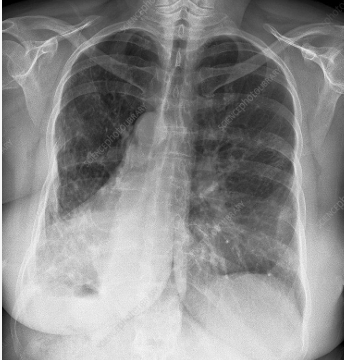

heart failure.

Detecting an enlarged heart, which can be a sign of

pulmonary edema

a common sign of congestive heart failure

fluid in the lungs